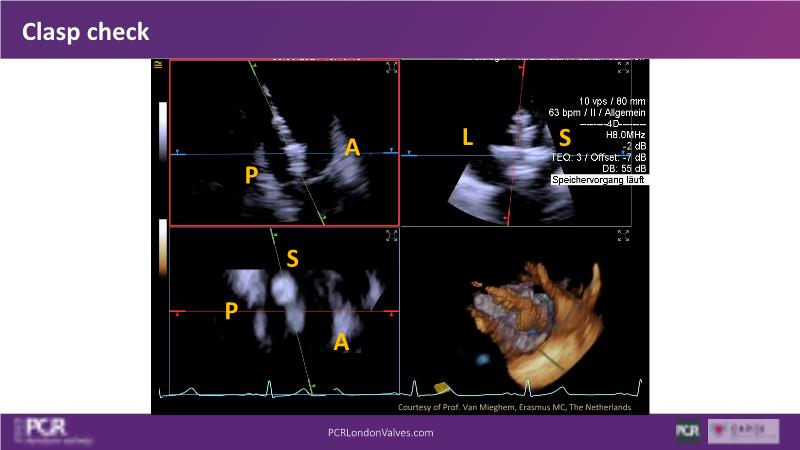

Expert roundtable: 4D ICE in tricuspid interventions

Join this session if you want to get familiar with the 4D ICE technology and the key elements of image guidance for tricuspid interventions, understand how 4D ICE can assist in specific procedural steps during challenging tricuspid interventions, and engage in an interactive discussion with experts about the current use of 4D ICE and insights into future developments.

- To get familiar with the 4D ICE technology and the key aspects of image guidance for tricuspid interventions

- To learn how 4D ICE can support specific procedural steps in challenging tricuspid interventions